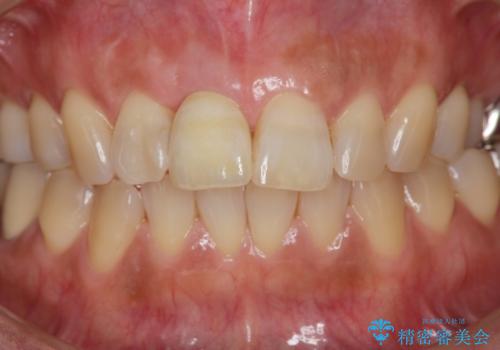

骨造成を伴う前歯のインプラント治療

前歯のインプラントを審美的に仕上げるには、インプラント周囲に十分な骨の量と厚みのある歯肉、そして埋入位置の精密な位置付けが重要です。